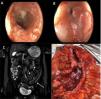

A 44-year-old woman had a past medical history of CD of the colon, diagnosed in 2013. She had multiple hospitalizations and was corticosteroid-dependent, with thiopurine refractoriness. In 2022, she was started on biologic therapy with infliximab due to perianal disease; later immune failure to that therapy resulted in switching her to adalimumab. Despite symptom improvement, biomarkers remained high (fecal calprotectin) and endoscopic examination revealed active CD in the rectosigmoid colon, with an uncrossable stricture in the sigmoid colon. (Fig. 1A and B). Magnetic resonance enterography (MRE) of the abdomen and pelvis identified inflammatory thickening of the walls of the distal third of the descending colon, the sigmoid colon, and the rectum, with small perirectal and presacral adenopathy (Fig. 1 C). Surgical treatment confirmed the stricture and inflammatory activity of the neighboring mucosa (Fig. 1D). The histopathologic study revealed CD activity with a transmural inflammatory infiltrate (Fig. 2A and B), foci of endometriosis in the stricture (Fig. 2C and D) with positive PAX 8 immunohistochemical staining (Fig. 2E and F), and the presence of estrogen receptors (Fig. 2G). The patient progressed satisfactorily, restarting biologic therapy 4 weeks after surgery.

A-B) Endoscopic study performed prior to surgery, showing erythematous and friable mucosa with multiple ulcers and an uncrossable stricture in the sigmoid colon. C) MRE showing a strictured area at the same site (white arrow). D) Surgical specimen after resection, showing a strictured area, with mucosal involvement and transmural extension.